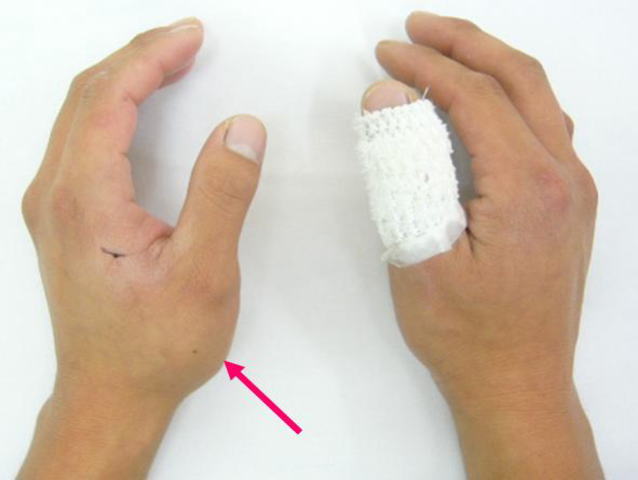

- 傷は縫合して密閉され、柔らかい包帯で覆われます。

親指にギプスを巻いてもらいます